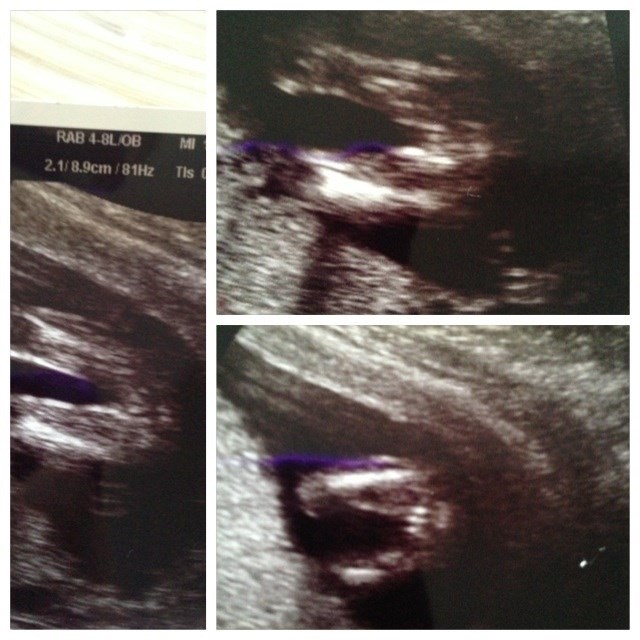

Nu jeg blevet i tvivl om vi virkelig venter en pige.Hvad ville i sige til det scannings billede?

Her er billeder af vores pige fra kønsscanning 14+.

Vedhæftede fotos (klik for at se i fuld størrelse)